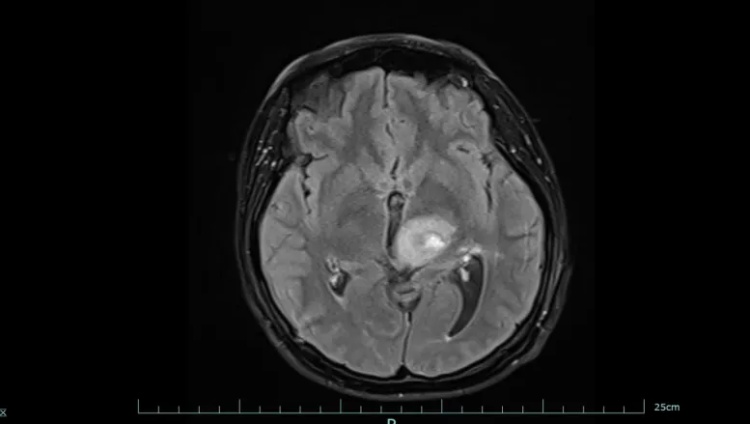

图一为治疗前,图二为治疗后

好在经过系统治疗,黄女士的肿瘤明显缩小,病情得到有效控制。目前,她已回归正常生活和工作,生活质量显著改善。